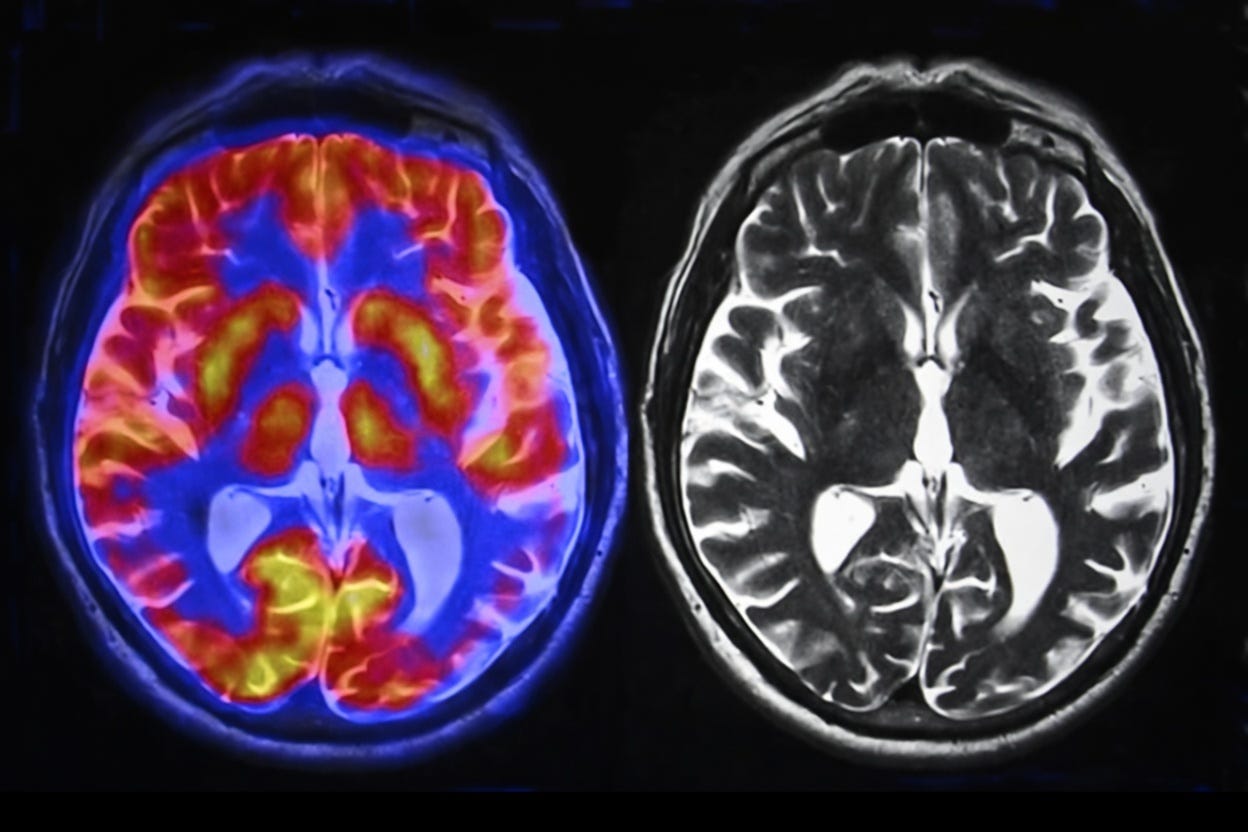

The Brain's Response to AI

Neuroimaging studies suggest that passive use of AI, like relying on chatbots for answers, actually suppresses brain activity. MIT's EEG study found that ChatGPT users displayed up to 55% weaker neural connectivity than those working unaided. But here's something intriguing: when AI is used as a tool rather than a crutch, such as in creative design tasks, brain engagement can increase. The real question is, are we asking AI to do too much of our thinking?